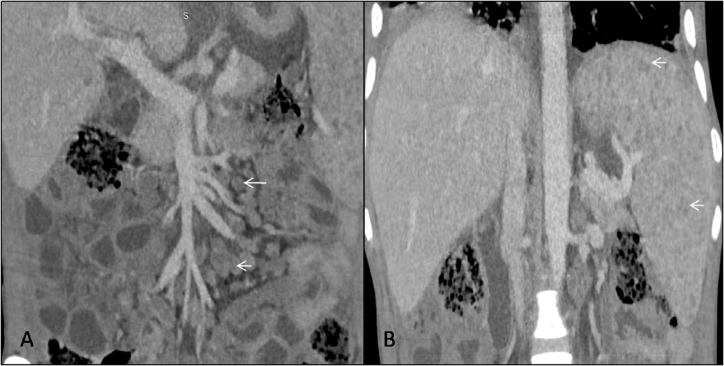

The scan was done on 128 slice Siemens CT scan machine, which revealed moderate hepatomegaly with liver measuring 17.5cm in craniocaudal dimension (Figure 1A). There were multiple conglomerated and enlarged lymph nodes with internal low attenuating areas (signify necrosis) observed in pre-para aortic, aortocaval and mesenteric regions (Figure 1B), largest measuring (20x11)mm in the right iliac fossa. The spleen was also enlarged with numerous tiny hypodense peripherally enhancing lesions diffusely scattered in its parenchyma (Figure 2). A minimal amount of free fluid was noted in the peritoneal cavity. The CT scan also demonstrated multiple centrilobular nodular densities arranged in linear branching patterns forming tree-in-bud appearance and patchy areas of consolidations in the limited scan of the bilateral lung fields (Figure 3A). Mild right-sided pleural effusions and left-sided empyema were also noted (Figure 3B).

Figure 1 Contrast enhanced computed tomography scan, venous phase in coronal plane, (A) shows multiple conglomerated, peripherally enhancing lymph nodes with central low attenuation in mesentery adjacent to mesenteric vessels (white arrow). (B) shows mild enlargement of the liver and spleen (craniocaudal length measures approx 17cm and 16cm respectively). Numerous tiny hypodense peripherally enhancing lesions are seen diffusely scattered insplenicparenchyma (white arrow).